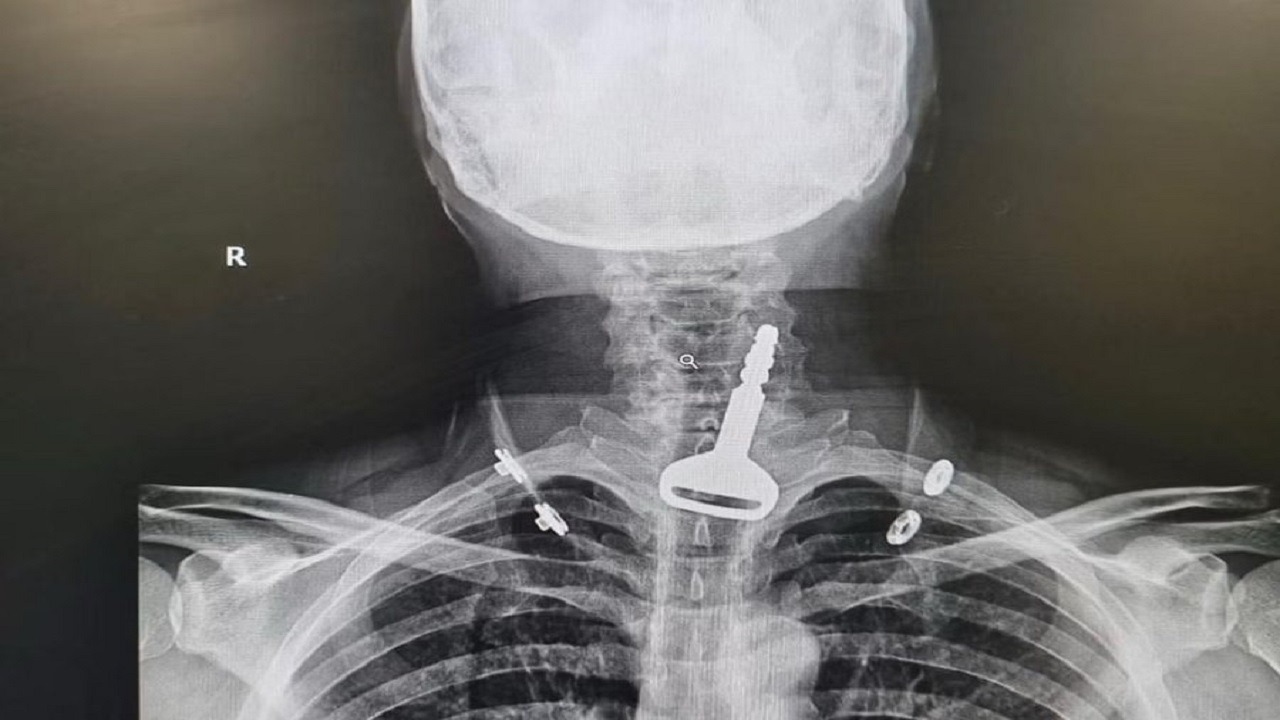

مفتاح سيارة كاد ينهي حياة أربعيني في القنفذة

نجاة طفل من الموت بأعجوبة بعد ابتلاعه “مفتاح” بالطائف